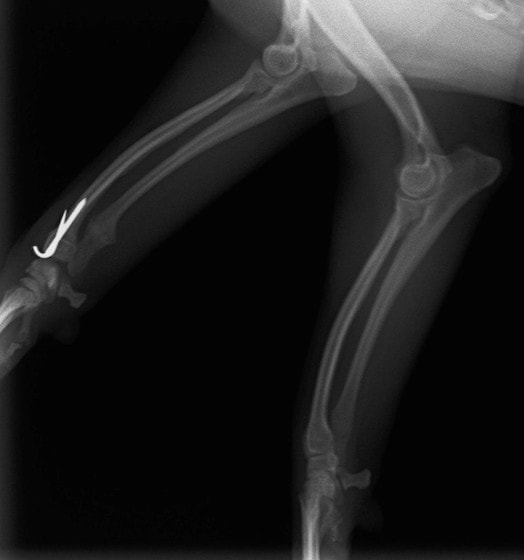

症例3:キルシュナーワイヤーのピンニングによる整復

ペルシャ猫 11ヶ月齢 雄

他院にて左大腿骨遠位の成長板骨折(salter-harrisⅠ型)が認められており、治療相談を目的として来院。当院にて、キルシュナーワイヤーを用いたピンニングにより骨折部位の整復を行いました。術後の経過は良好で、現在も経過観察中です。

術前レントゲン

術後レントゲン

機器

Arthrex社のターゲティングデバイスを用いてピンニングの位置を調整することで、確実な固定を行っています。当院ではこの手術器具以外にも、人の手術にも使用される様々な器具を導入し、手術精度を高め、また医療メーカーと新しい器具の開発、試作にも取り組んでおります。